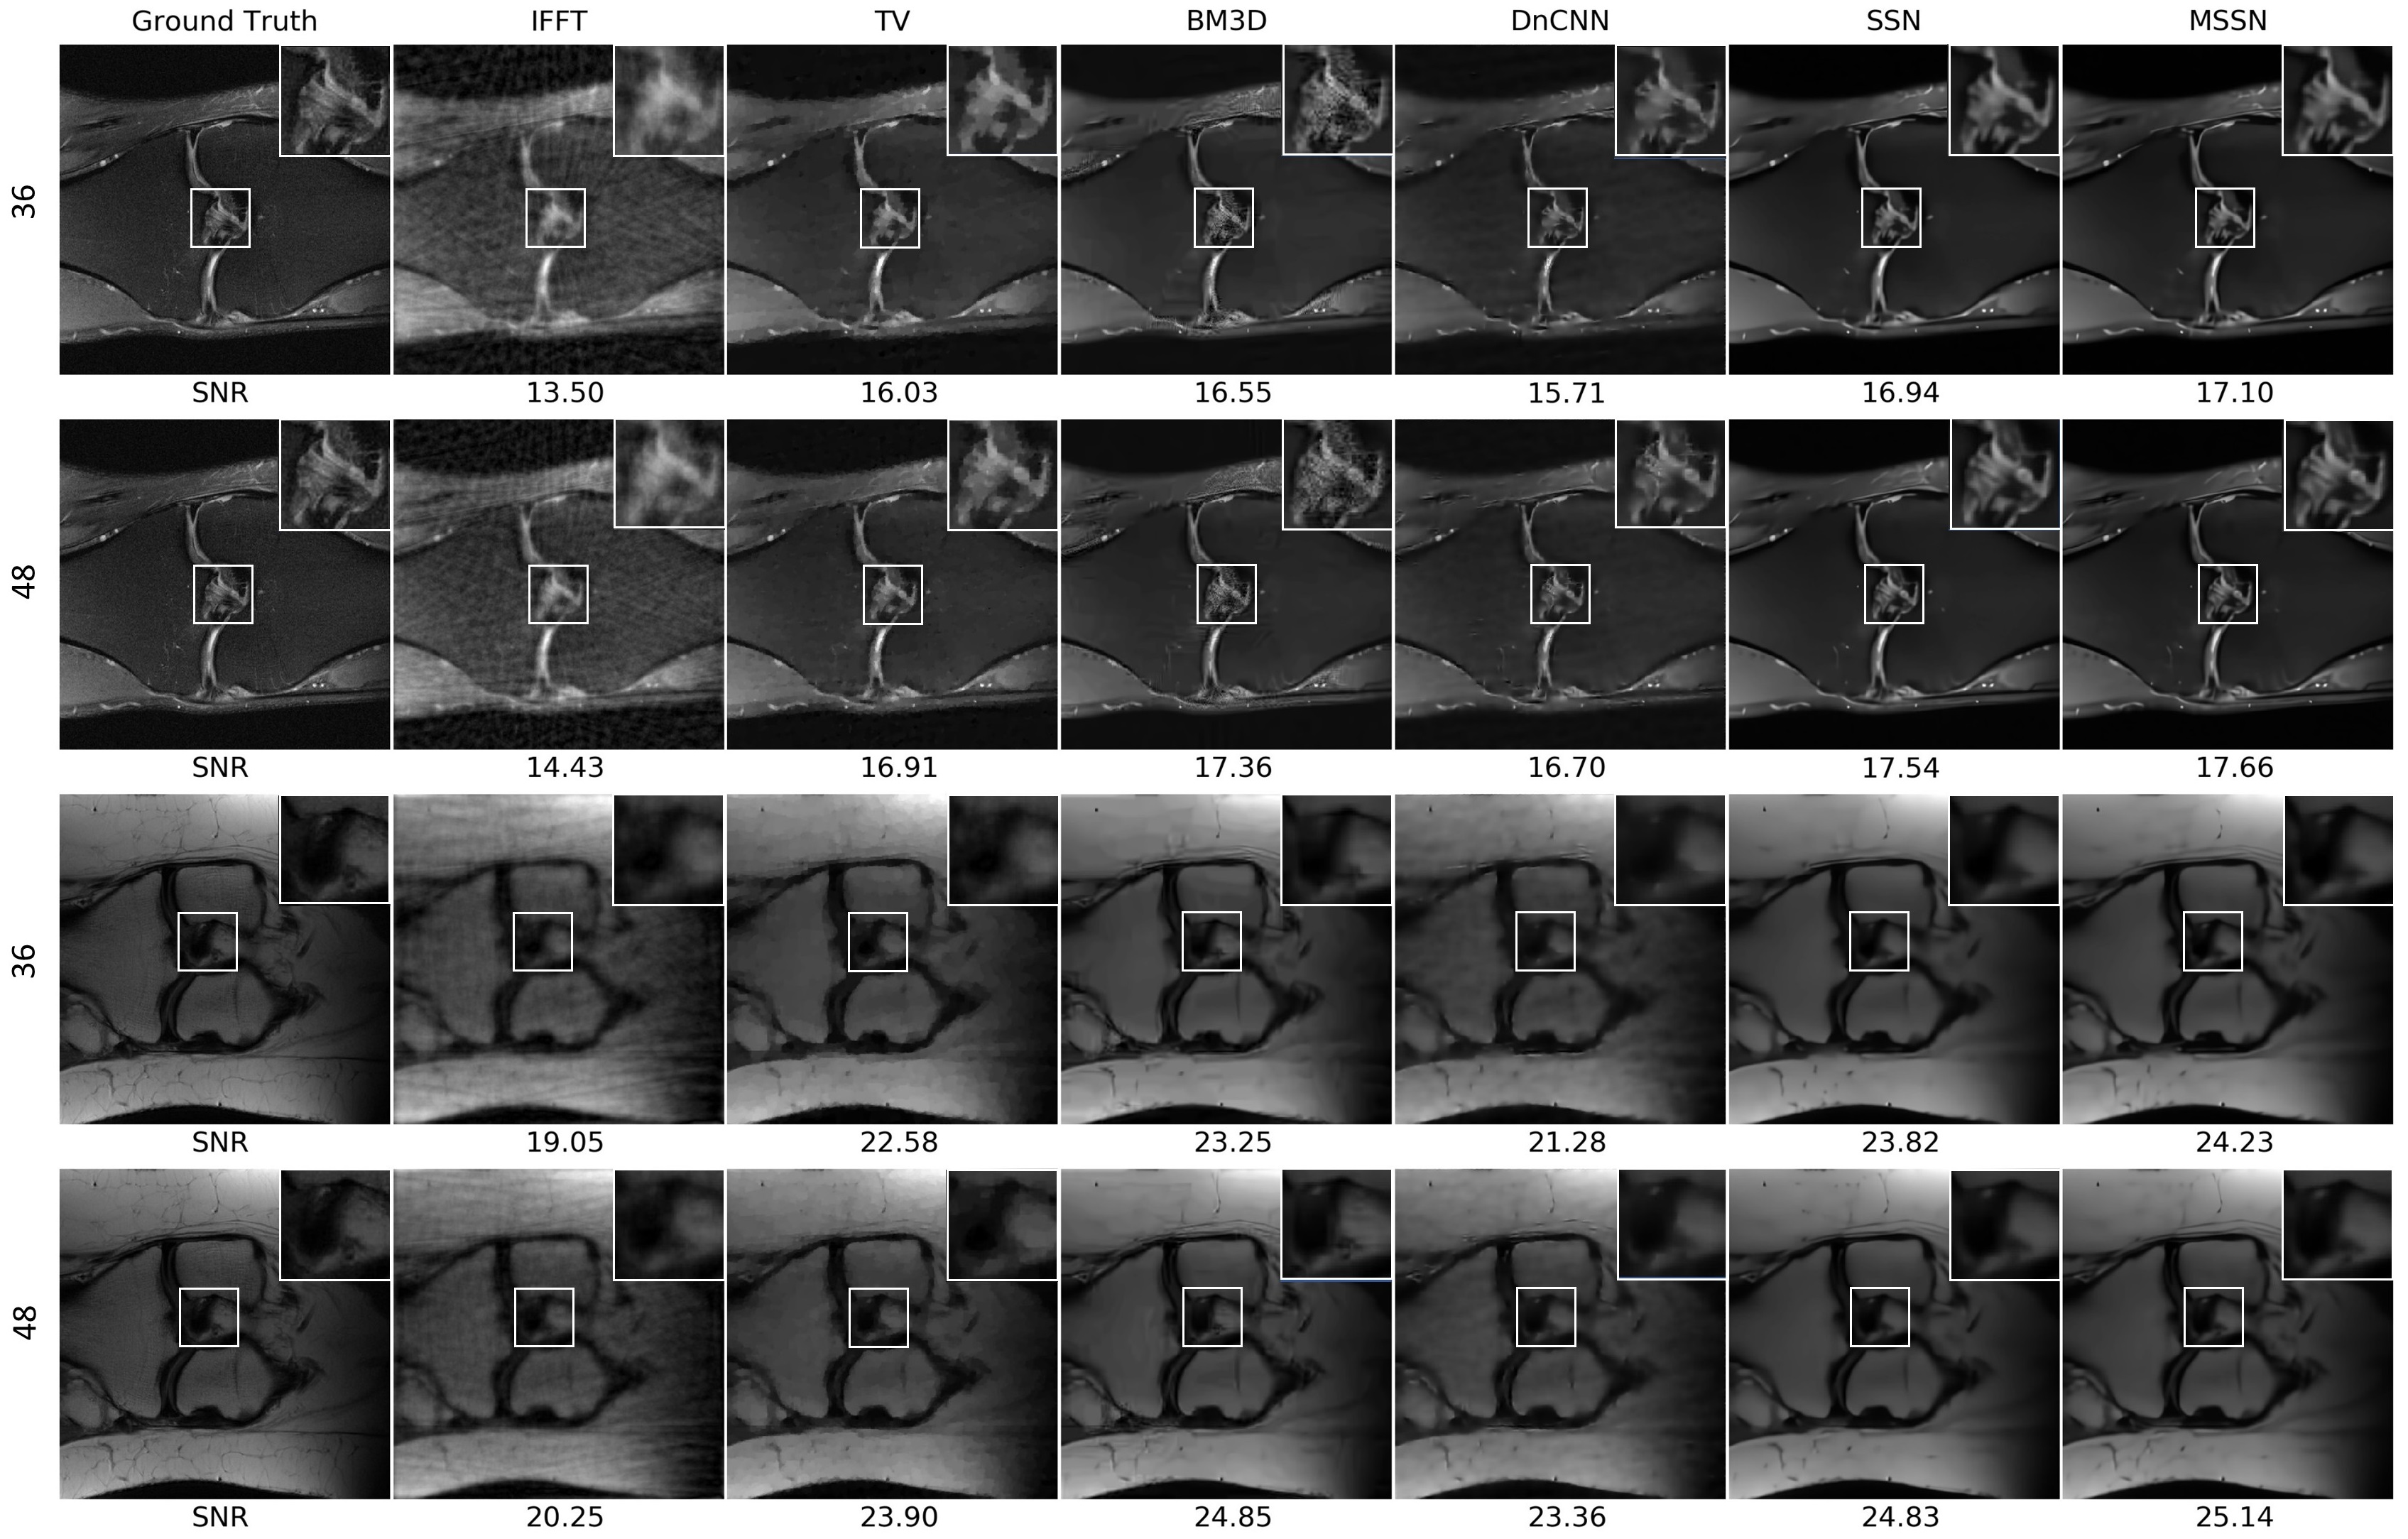

Figure 2 demonstrates the details of the MRI reconstruction. The first two rows are the reconstruction results of no. 58 in fastMRI dataset using 36-lines and 48-lines radial sampling respectively. The last two rows are results of no. 21119. Visual inspection of reconstructed images reveals that proposed denoiser is robust in these two T1, T2-weighted MR images of bones, and artefacts are diminished using SSN or MSSN denoiser compared to conventional denoisers. More crucially, PnP algorithm using MSSN keeps subtle yet important anatomical details and offers more faithful reconstructions that can be recognized in the zoomed-in views.

Refer to caption

Figure 2: Illustrations of MRI reconstruction from k𝑘k-space downsampled data (no. 58 and no. 21119 using radial sampling, the first and third rows use 36 lines for sampling and the second and the fourth rows use 48 lines) using different denoisers within PnP. Each reconstruction is labeled with its SNR (dB) value with respect to the ground truth.